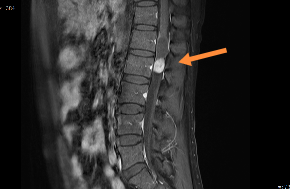

幾經(jīng)周折后,吳先生來到惠州市第三人民醫(yī)院就診,經(jīng)檢查最終被確診為椎管內(nèi)腫瘤。

磁共振

惠州三院神經(jīng)外科專家文世宏主任說:“椎管內(nèi)腫瘤可壓迫脊髓和神經(jīng),引起肢體運(yùn)動(dòng)和感覺障礙。許多椎管內(nèi)腫瘤患者都和這位患一樣,癥狀隱匿,常常被誤認(rèn)為是腰椎間盤突出癥或腰肌勞損,延誤了治療。同時(shí),椎管內(nèi)腫瘤的診斷需要進(jìn)行仔細(xì)的查體,然后通過CT、磁共振等影像學(xué)檢查進(jìn)一步明確病變。”